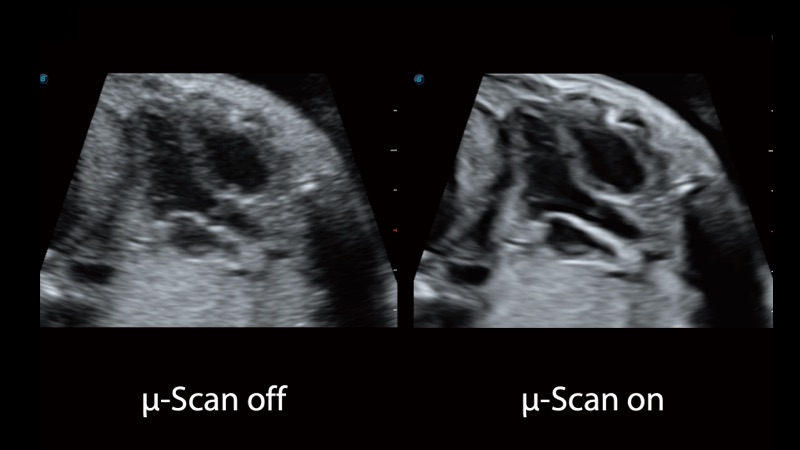

開立醫(yī)療通過不斷的技術(shù)創(chuàng)新,為大眾的生命健康提供持續(xù)關(guān)愛。P12 Plus采用全新一代超聲成像平臺,新平臺旨在將真實還原組織解剖結(jié)構(gòu)作為首要目標(biāo)。平臺采用全新集成化硬件模塊,搭載新一代芯片,系統(tǒng)性能得到大幅提升,為您的診斷提供了豐富的臨床信息。優(yōu)異的圖像表現(xiàn),豐富的探頭配置,全面的應(yīng)用功能,為您日常診斷提供了可靠的助手。